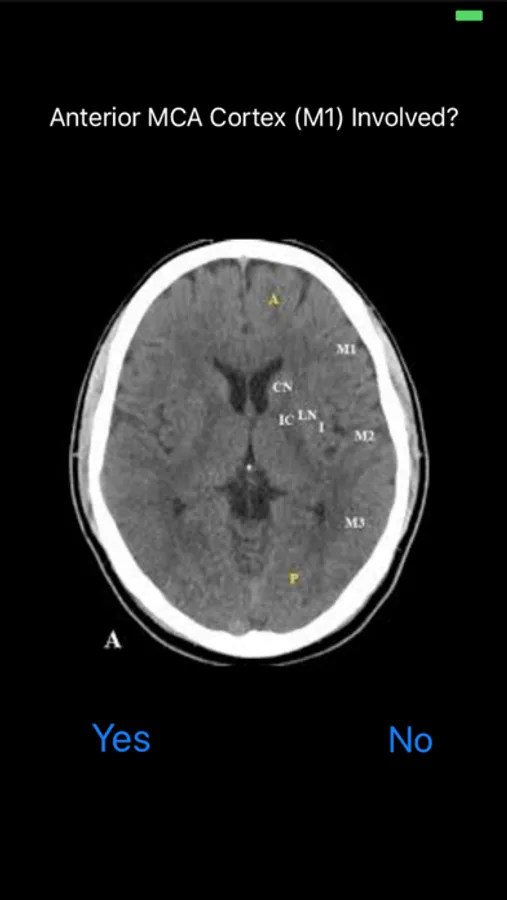

An application for healthcare providers to help calculate an ASPECTS score when you need it most!